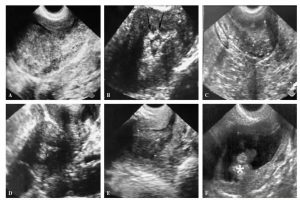

Diplomados en Ultrasonografía